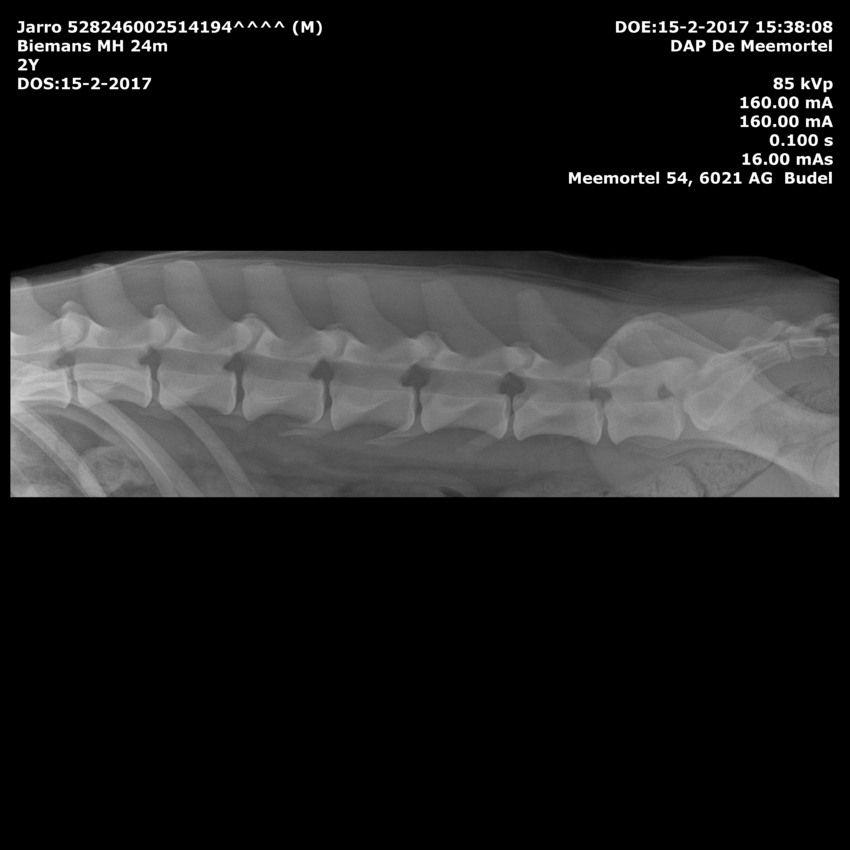

Jarro rontgen van maurice